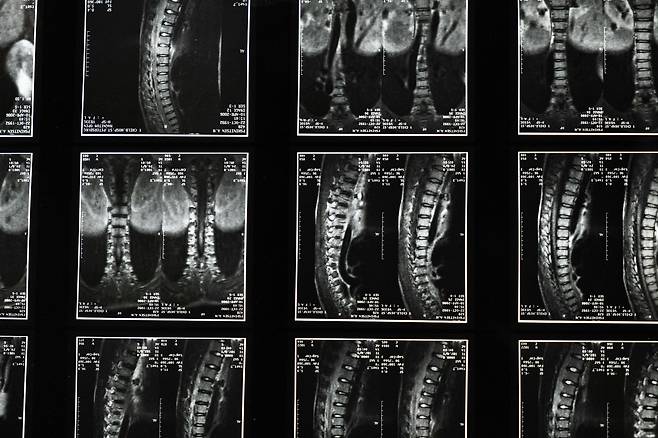

척추 MRI, 급여 되는데 비급여로 내는 사람 많습니다

2022년 3월부터 척추 MRI가 건강보험 급여 대상으로 확대됐습니다. 허리디스크, 척추관협착증, 척추 협착 같은 퇴행성 질환이 의심되면 급여로 찍을 수 있습니다.

급여 적용 시 비용

- 비급여: 40~70만원

- 급여 적용: 10~20만원 (본인부담금)

급여 대상 척추 질환

- 척추간판탈출증 (허리디스크, 목디스크)

- 척추관협착증

- 척추전방전위증

- 척추 골절

- 척추 종양 의심

- 척추 감염 의

이런 진단이 나오거나 의심된다면 MRI는 급여 대상입니다. 반드시 물어보세요.